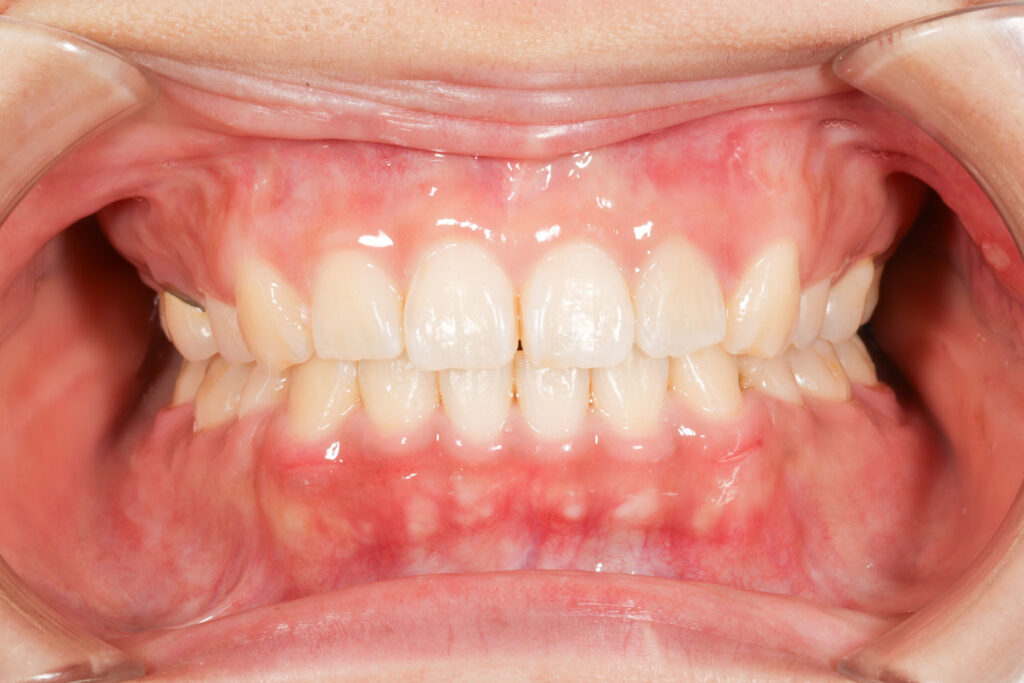

Before

After

年齢 10代

治療装置 上は裏側の矯正装置(ハーフリンガル)

治療内容 上下左右4本抜歯

治療期間 2年8か月

リスク 歯の移動に伴う痛み、歯肉退縮、歯根吸収、歯肉炎、虫歯

主訴 八重歯が気になる

症状 叢生(ガタガタ)

治療回数 33回程度

総額費用 125万円程度